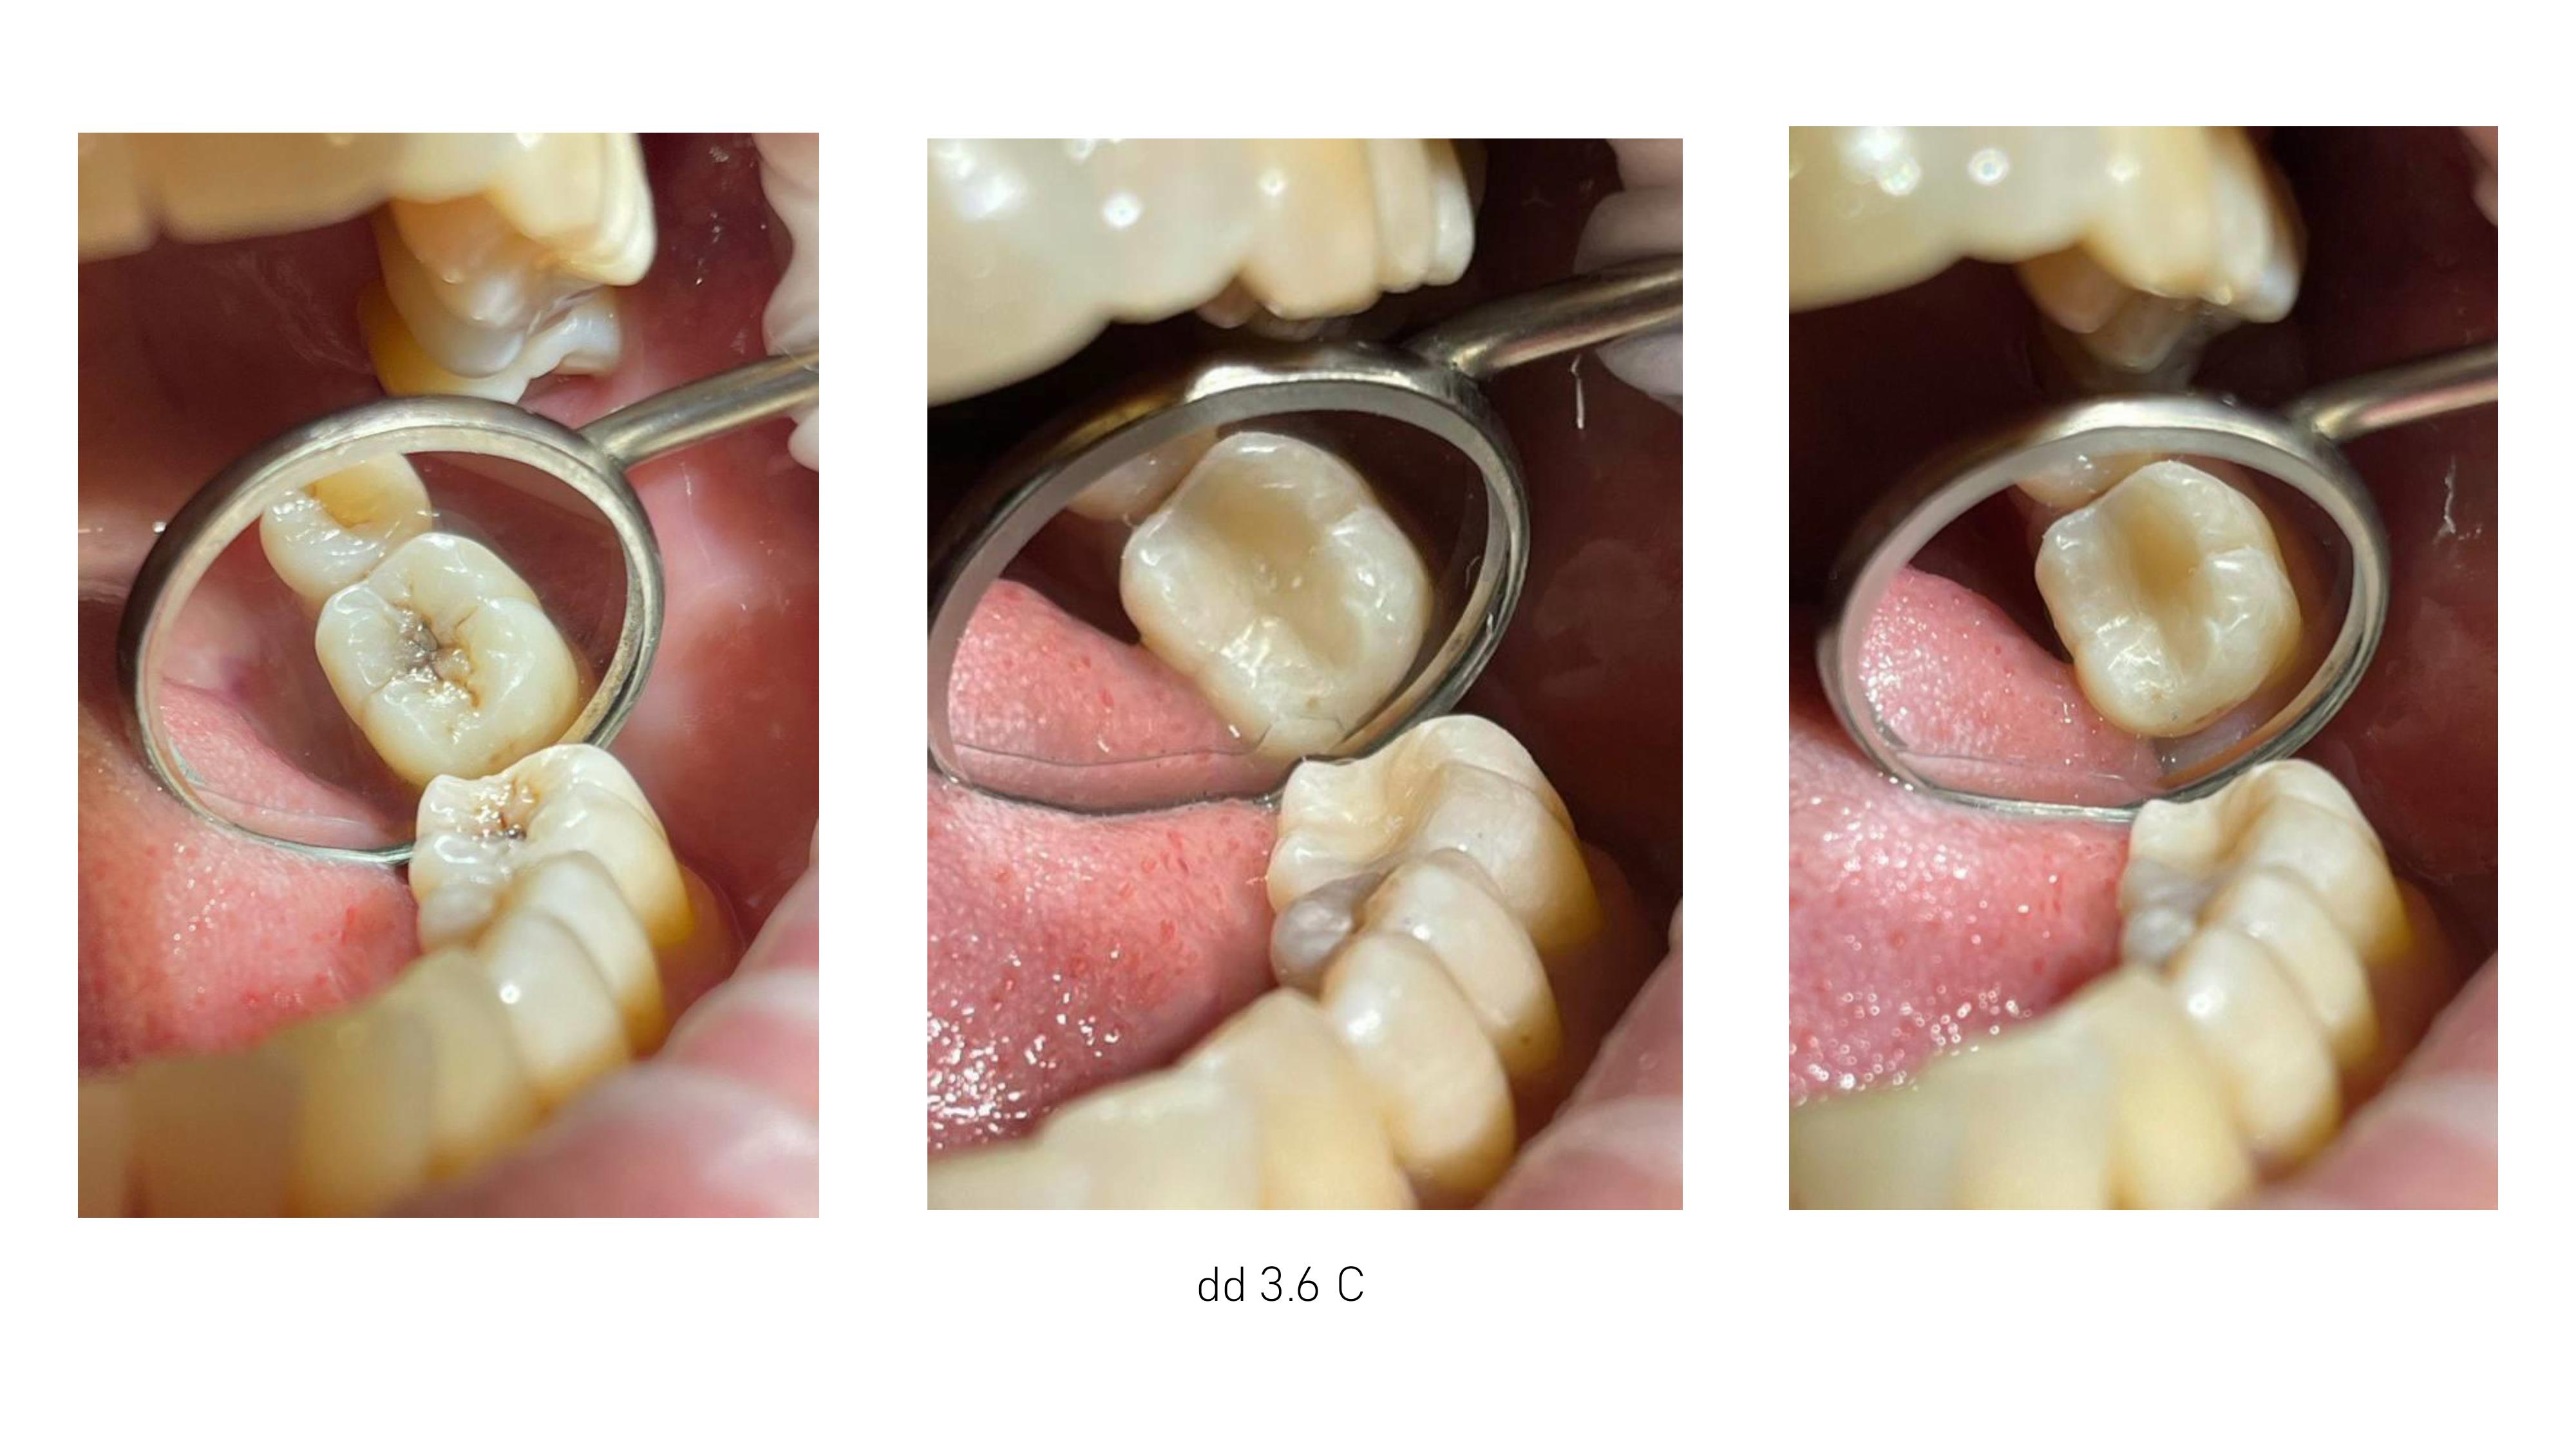

6. Диагностика и лечение кариеса временных и постоянных зубов с использованием микроскопа, лечение пульпитов и периодонтитов временных и постоянных зубов.